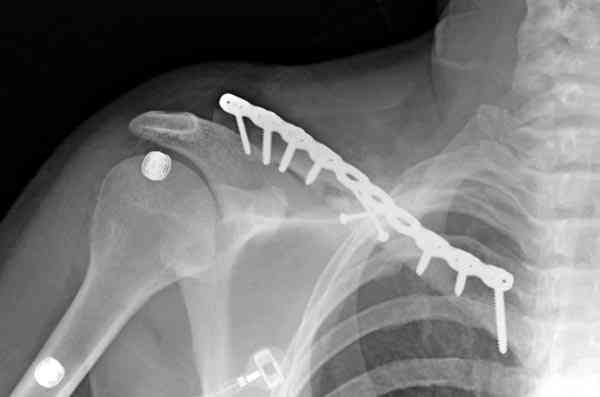

Описанный случай это больная моего партнера, мы недавно случай разбирали на нашей конференции (Morbidity and Mortality Conference аналог клинического разбора)

Выставлен как пример, к чему может привести

неудачно выбранный фиксатор.

Больные иногда пропадают из нашего поле зрения, ту больную неудачно оперировал в нашем городе специалист по спортивной медицине. Он же направил к нам после удаления фиксатора.